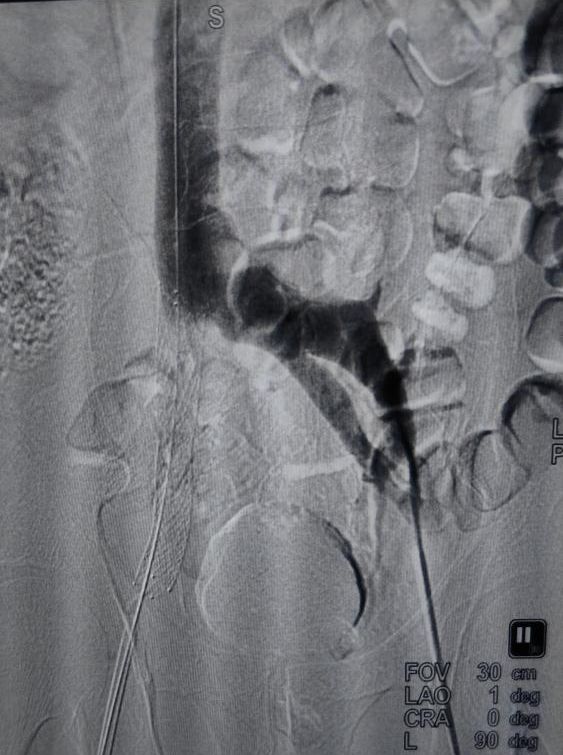

针对这一复杂病因,传统手术方式往往难以有效解决。我院外周介入团队经过充分评估,决定为患者实施目前先进的“髂静脉支架置入术”。手术在数字减影血管造影(DSA)引导下进行,通过微创穿刺,精准定位受压的髂静脉段,成功植入一枚专用血管支架。支架撑开了被压迫的血管,瞬间恢复了静脉血流的通畅。手术过程顺利,患者术后恢复良好,下肢不适症状得到显著缓解。